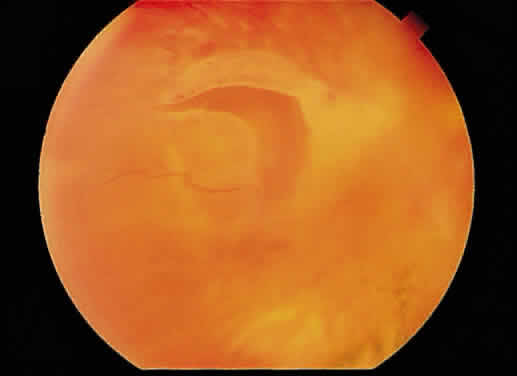

Fig. 25. Fundus photograph of cytomegalovirus retinitis with the classic admixture

of retinal infection (white) and hemorrhage, giving the so-called “pizza-pie” appearance. Fig. 25. Fundus photograph of cytomegalovirus retinitis with the classic admixture

of retinal infection (white) and hemorrhage, giving the so-called “pizza-pie” appearance.